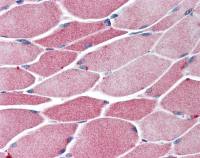

IHC-P analysis of human skin tissue section using GTX02665 Cytokeratin 2 antibody [KRTH/4392R].

IHC-P analysis of human skin tissue section using GTX02665 Cytokeratin 2 antibody [KRTH/4392R].